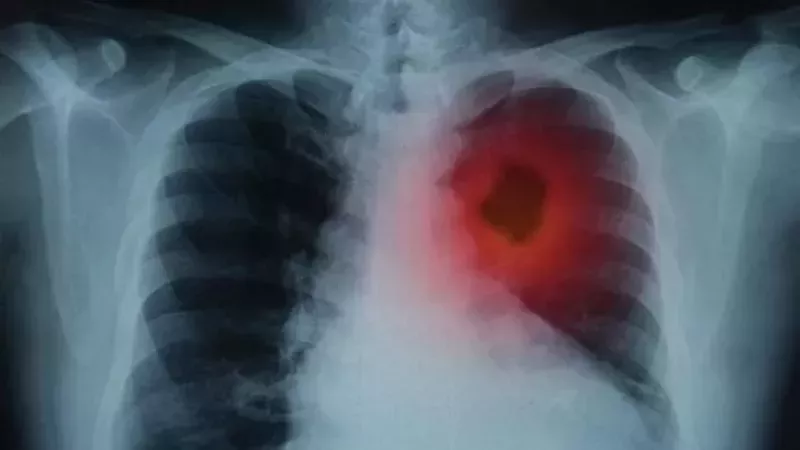

Akciğer embolisi, akciğer arterlerinde bir pıhtı, hava kabarcığı ya da bir materyal sebebiyle kan akışının tıkanması sonrası meydana gelen bir durum olmaktadır. Bahsi geçen bu tıkanma, akciğerinin oksijen alışverişini bozulmasına ve ciddi solunum problemlerine neden olabilir. Akciğer embolisi nasıl meydana gelir? İşte merak edilen detaylar!

Akciğer embolisi, tipik olarak bir derin ven trombozu (DVT) sonrasında meydana gelmektedir. DVT, bacaklardaki derin venlerde kan pıhtılaşmasıyla karakterize durumdadır. Bu pıhtılar, kan akışının akciğerlere kadar gitmesinin önüne geçen akciğer arterlerinin bir bölgesinde sıkışma meydana getirebilir. Akciğer embolisi, akciğer alterlerinde bir pıhtı, yağ, hava kabarcığı ya da başka bir materyal sebebiyle kan akışının tıkanması sonrasında oluşan bir durum olmaktadır. Bu tıkanma, akciğerlerin oksijen alışverişinin bozulmasına ve ciddi sorunların meydana gelmesine sebep olabilir.

Bu hastalığın belirtileri içerisinde; nefes almakta zorluk, göğüste ağrı meydana gelmesi, öksürük, kanlı balgam, hızlı bir şekilde kalp atışı, terleme ve halsizlik yer almaktadır. Akciğer embolisi tedavisi ise pıhtıların büyüklüğüne ve yayılımına, hastanın yaşla sağlık durumuna, varsa altta yatan sorunlara ve diğer faktörlere bağlı olarak değişim göstermektedir. Antikoagülan ilaçlar, cerrahi müdahale, trombolitik ilaçlar ve aspirin seçenekler arasında yer almakta.